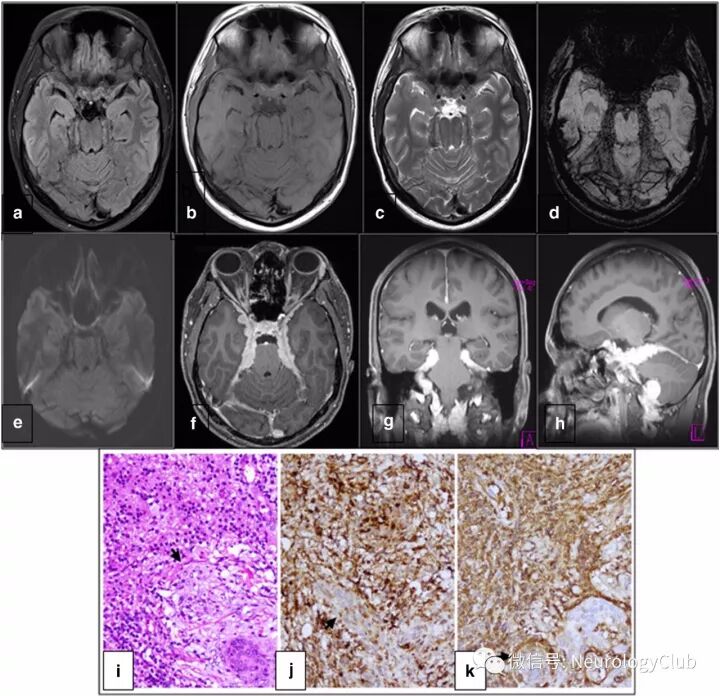

(图:a-c:FLAIR,T1WI和T2WI可见广泛基于硬脑膜的低信号病变;d:SWI可见内部散在多发低信号;e:DWI未见弥散受限;f-h:增强后可见弥漫硬脑膜病灶均匀强化;i:HE染色可见淋巴细胞,浆细胞和苍白大组织细胞浸润,伸入现象不明显;j-k:组织细胞CD68和S-100免疫组化染色阳性,而内皮细胞阴性

35岁男性,2009年10月入院,表现为持续性慢性枕部钝痛和颈痛18月,伴进行性视物模糊、双侧听力下降以及单侧耳鸣3月。外院(2009年7月)头颅MRI提示视神经异常信号伴鞍上区广泛结节样脑膜增厚并强化,延伸至眼眶。脑脊液淋巴细胞480个,蛋白92mg/dL,糖85mg/dL。当时考虑结核性脑膜炎,予抗结核药物(ATT)联合激素治疗。患者症状开始有轻微改善,后再次恶化。本次我院查体提示患者意识清,右眼能分清2米外手指,而左眼仅有光感,双侧视神经萎缩,双侧严重的感音神经性耳聋。复查头颅MRI可见轻度脑室扩大和脑膜强化。脑脊液淋巴细胞110个,蛋白129mg/dL,糖36mg/dL。脑脊液VDRL阴性。血清ACE水平35.3U/L(正常值:8-52)。ANCA检测阴性。2009年11月复查脑脊液,淋巴细胞385个,蛋白156mg/dL,糖56mg/dL。患者继续ATT和激素治疗,症状平稳。2010年8月,患者激素逐渐减量,视力下降和头痛再次出现。听力完全丧失。此时添加硫唑嘌呤,ATT和激素继续维持。但患者视力持续恶化,并有轻度弥漫性头痛。最后一次腰穿脑脊液淋巴细胞28个,蛋白559mg/dL,糖21mg/dL。复查头颅MRI(2011年4月)可见广泛硬脑膜病变,累及双侧鞍旁区,鞍结节,蝶骨平台和小脑幕。向下累及斜坡延伸至颈椎。双侧桥小脑角亦受累。病灶延伸至双侧内听道和右侧舌下神经管。病灶在T1WI上呈等信号,T2WI上为低信号。SWI上可见病灶内散在多发小点状低信号。DWI未见弥散受限。增强可见病灶明显均匀强化。